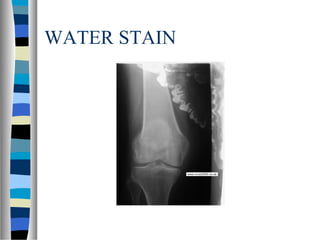

WATER STAIN